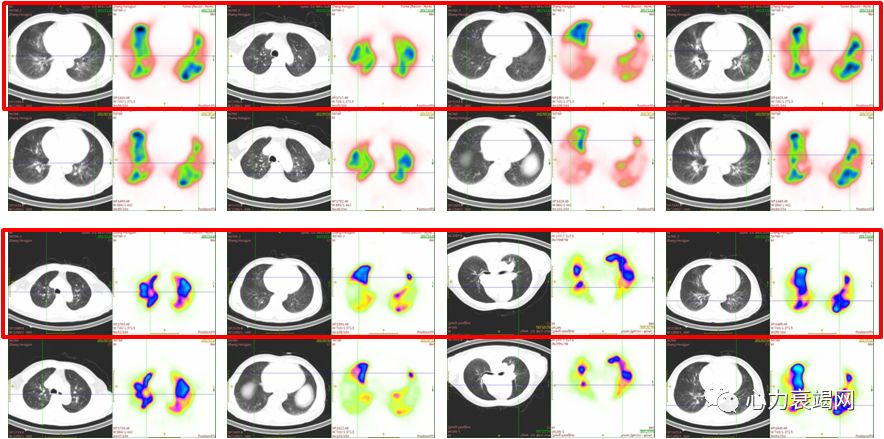

2017-04-18肺通气/灌注扫描:左肺下叶外基底段、右肺下叶前基底段和外基底段肺栓塞高度可能

2017-04-20CTPA:左下肺动脉、右下肺动脉分支充盈缺损

肺通气/灌注扫描:左肺上叶及下叶、右肺上叶、中叶及下叶肺栓塞高度可能

右肺中叶外侧段、内外基底段、左肺上叶舌段、下叶内基底段灌注明显改善

右肺上叶尖段、前段、后段、右肺中叶内侧和外侧段、右肺下叶背段和内外基底段、左肺上叶尖后段、前段、舌段、左肺下叶前内基底段、外基底段灌注改善

球囊扩张术后右肺上叶前段和后段、右肺中叶内侧段、左肺上叶尖后段和舌段、左肺下叶外基底段和后基底段肺灌注增加